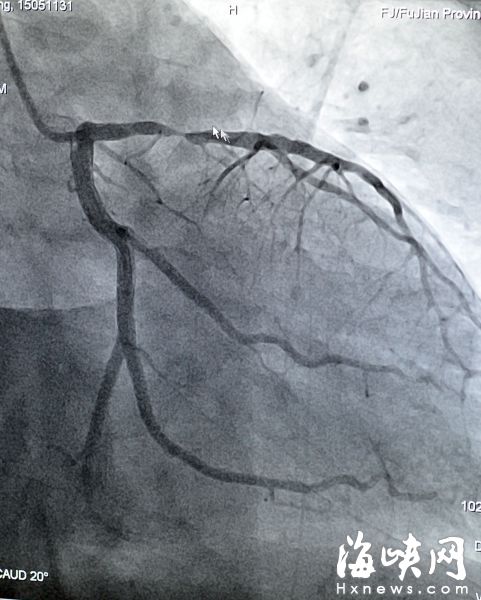

近距直击心脏支架手术 堪称命悬一线的交战

481x600 - 52KB - JPEG